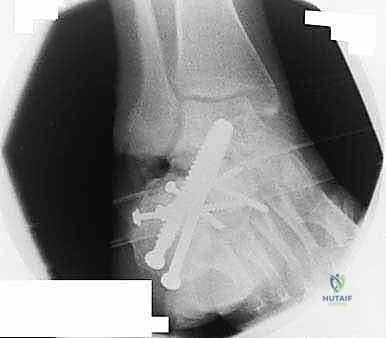

2. التصوير بالأشعة السينية (X-rays) مع تحمل الوزن

صور الأشعة السينية هي الخطوة الأولى. يطلب د. هطيف صوراً بوضعيات محددة (أمامية خلفية، جانبية، ومحورية Harris view) لتقييم:

* زاوية بوهلر (Böhler's angle) وزاوية جيسان (Gissane's angle) لتقييم فقدان الارتفاع والانخساف.

* مدى اتساع الجدار الجانبي.

* علامات التهاب المفاصل (تضيق المسافة المفصلية، تكون نتوءات عظمية، وتصلب العظم تحت الغضروف).